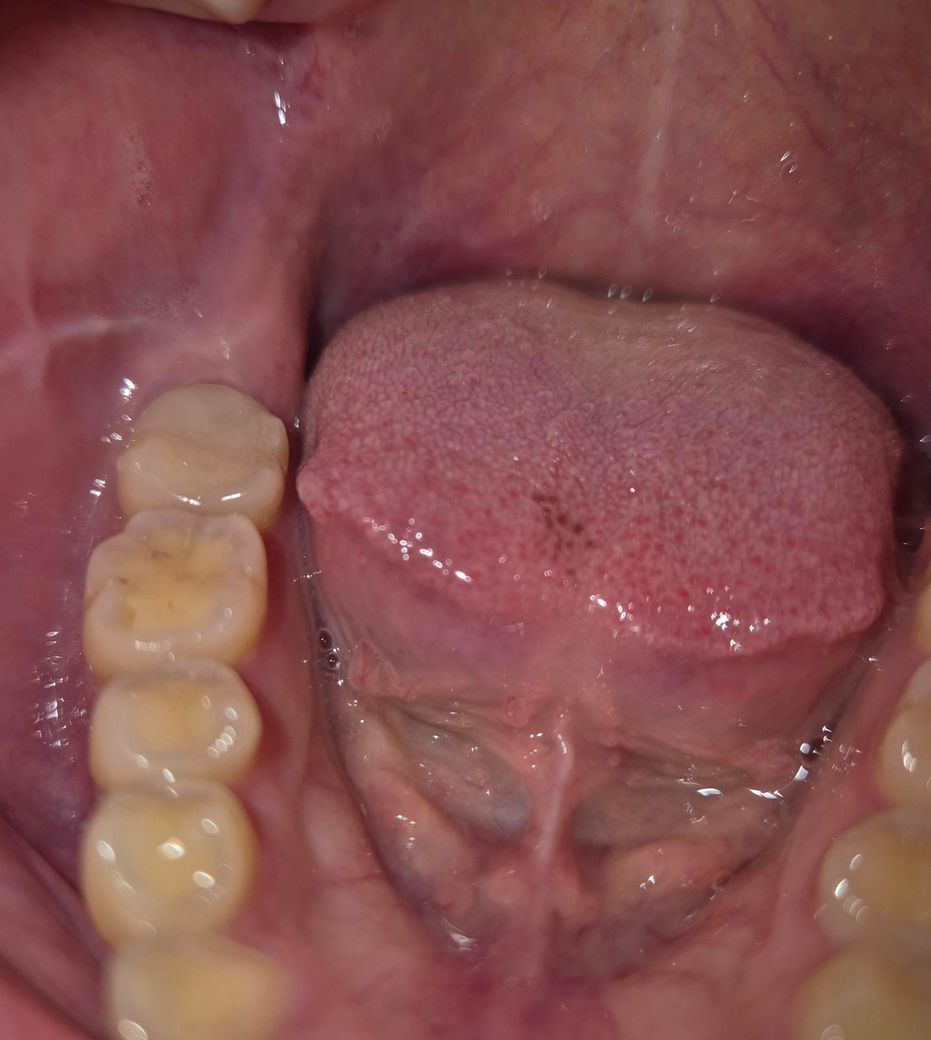

오른쪽 밑 맨 뒤 어금니가 문지르면 아파요.

밥 먹을 때나 뭐 마실 때 시린 건 없는데 혀로 문지르거나 손으로 문지르면 아프더라구요 윗부분이..

해당 치아 자체에는 그다지 문제가 보이지는 않아서 사랑니로 인한 통증일 확률도 있겠습니다.

오른쪽 밑 맨 뒤 어금니가 문지르면 아파요. -> 사랑니가 영향을 줬을 가능성이 있습니다. 다른 치과도 가보세요

치아에 과도한 힘이 가해지거나 하면 예민해 지기 때문에 혀가 닿는 자극에 불편감이 있을수 있습니다.

이런경우 치아에 가해지는 힘을 줄여본다면 해당증상이 줄어들게 됩니다.

보철물의 접착이 잘되있지 않은 경우에도 증상이 있을수 있으며 접착이 잘 되어 있지 않다면 보철물ㅇㄹ 새로 제작해야할수 있습니다.